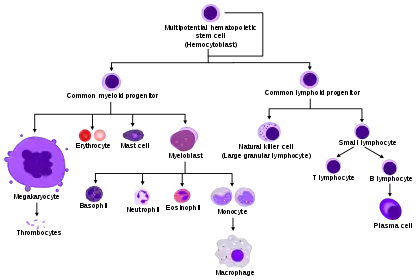

Eosinophils, sometimes called eosinophiles or, less commonly, acidophils, are a variety of white blood cells and one of the immune system components responsible for combating multicellular parasites and certain infections in vertebrates.[2] Along with mast cells and basophils, they also control mechanisms associated with allergy and asthma. They are granulocytes that develop during hematopoiesis in the bone marrow before migrating into blood, after which they are terminally differentiated and do not multiply.[3] They form about 2 to 3% of WBCs.

TH2 and ILC2 cells both express the transcription factor GATA-3, which promotes the production of TH2 cytokines, including the interleukins (ILs).[6] IL-5 controls the development of eosinophils in the bone marrow, as they differentiate from myeloid precursor cells.[6][10][11][12] Their lineage fate is determined by transcription factors, including GATA and C/EBP.[3] Eosinophils produce and store many secondary granule proteins prior to their exit from the bone marrow. After maturation, eosinophils circulate in blood and migrate to inflammatory sites in tissues, or to sites of helminth infection in response to chemokines like CCL11 (eotaxin-1), CCL24 (eotaxin-2), CCL5 (RANTES), 5-hydroxyicosatetraenoic acid and 5-oxo-eicosatetraenoic acid, and certain leukotrienes like leukotriene B4 (LTB4) and MCP1/4. Interleukin-13, another TH2 cytokine, primes eosinophilic exit from the bone marrow by lining vessel walls with adhesion molecules such as VCAM-1 and ICAM-1.[6] When eosinophils are activated, they undergo cytolysis, where the breaking of the cell releases eosinophilic granules found in extracellular DNA traps.[6] High concentrations of these DNA traps are known to cause cellular damage, as the granules they contain are responsible for the ligand-induced secretion of eosinophilic toxins which cause structural damage.[6] There is evidence to suggest that eosinophil granule protein expression is regulated by the non-coding RNA EGOT.[13]